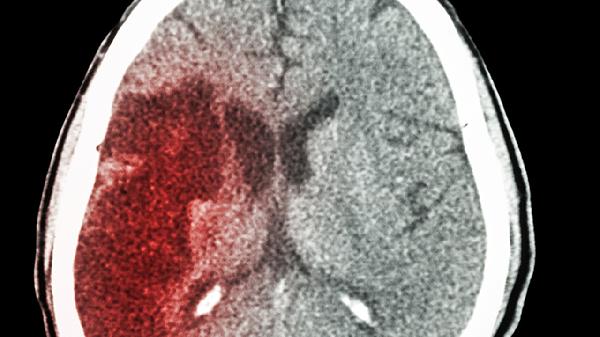

脑出血一年后脑神经功能存在恢复可能,恢复程度主要取决于出血部位、出血量、康复治疗介入时机与持续性、患者基础健康状况及年龄等因素。

脑出血后一年内是神经功能恢复的关键时期,此阶段大脑的可塑性较强,通过系统性康复训练可促进神经通路重建。康复措施包括物理治疗如关节活动度训练与平衡协调练习,作业治疗如日常生活活动训练与精细动作练习,言语治疗针对失语或构音障碍进行干预,以及认知训练改善记忆与执行功能。坚持规范康复能有效提升运动、语言及认知能力,改善生活质量。部分患者可能出现肌张力增高,即痉挛,影响肢体活动,需在康复师指导下进行牵伸与体位管理。高压氧治疗可作为辅助手段,增加血氧含量,促进受损神经组织修复。营养支持同样重要,适当增加优质蛋白与B族维生素摄入有助于神经修复。

脑出血一年后神经恢复速度可能减缓,但并未完全停止。长期遗留的功能障碍如偏瘫、吞咽困难或认知下降,仍需持续康复维持现有功能并争取进一步改善。心理疏导有助于缓解卒中后抑郁或焦虑情绪,对康复有积极影响。对于严重痉挛或其他并发症,可考虑肉毒毒素注射等医疗干预。患者年龄、基础疾病如高血压或糖尿病控制情况,以及卒中复发预防措施的执行程度,都会影响远期恢复效果。定期随访评估,根据恢复情况调整康复方案,对长期功能维持至关重要。